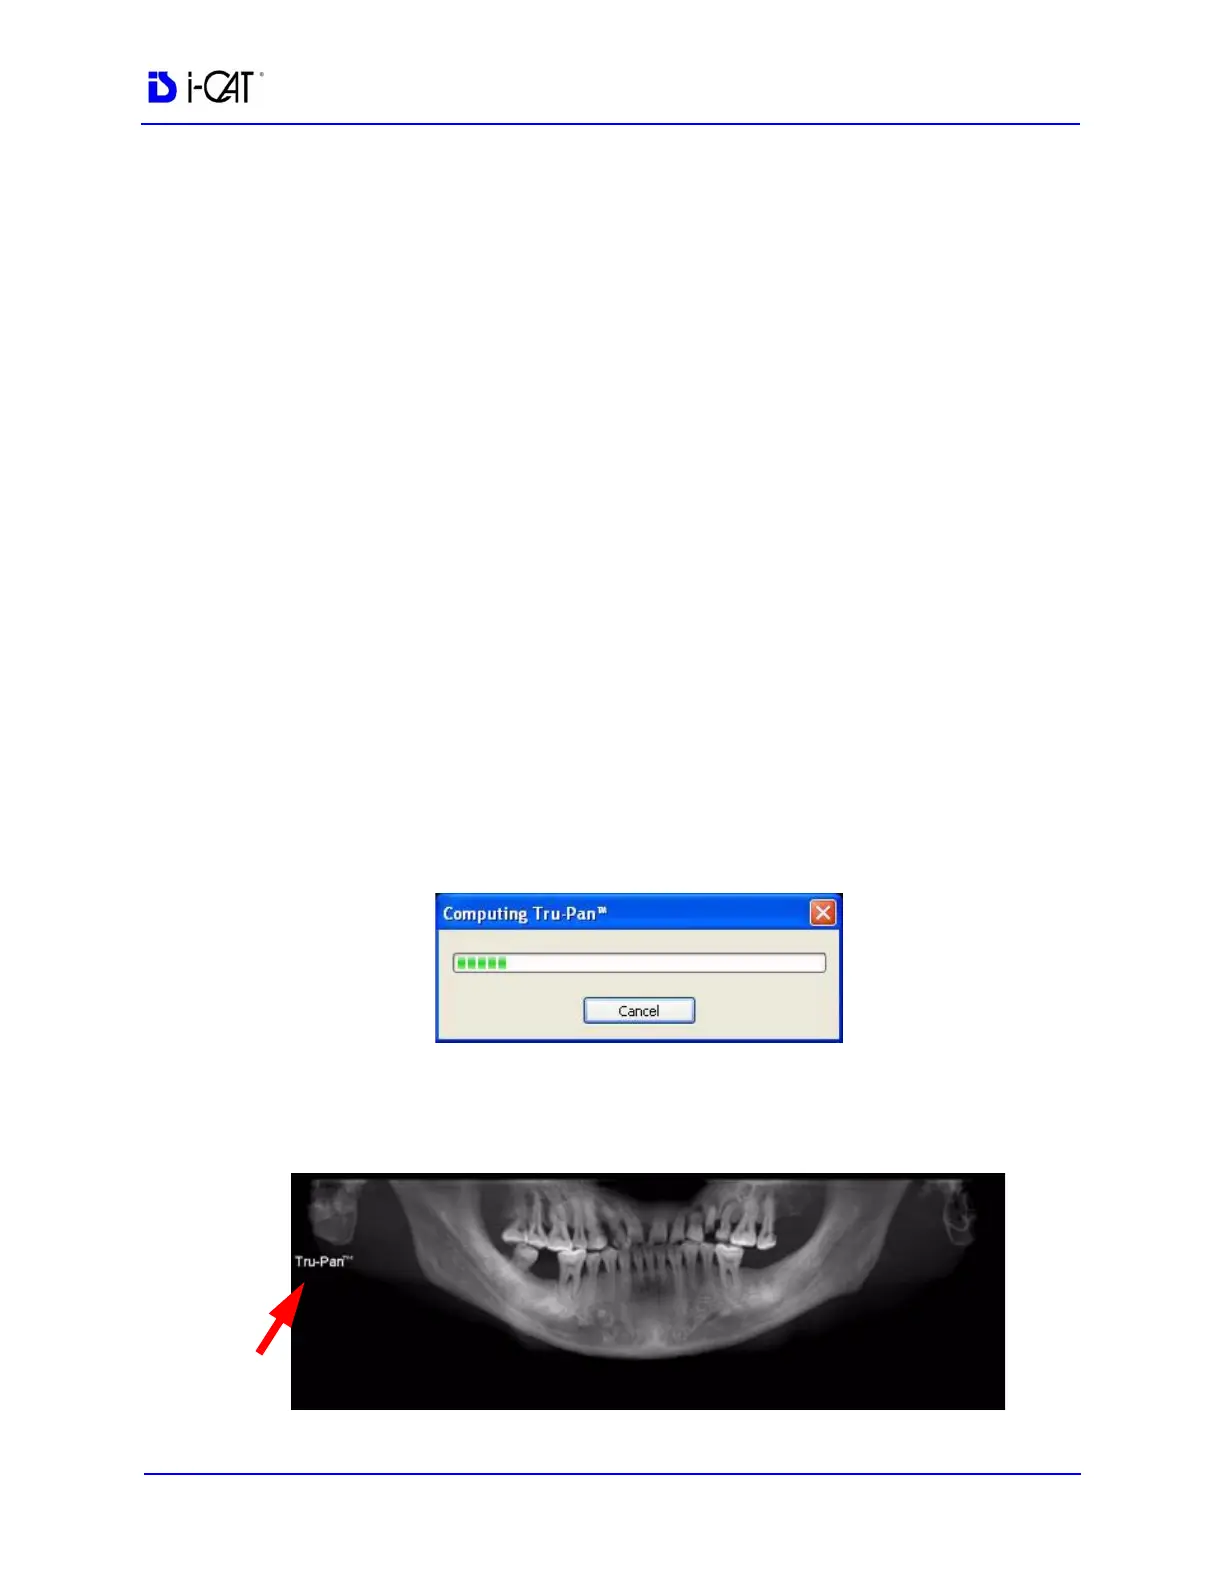

After selecting a study from the Study List, the Tru-Pan dialog is

displayed while the image is rendering.

It may take up to 2 1/2 minutes for the Tru-Pan image to compute,

depending on the resolution of the study. Tru-Pan images are

displayed with a Tru-Pan tag on the Panoramic View.